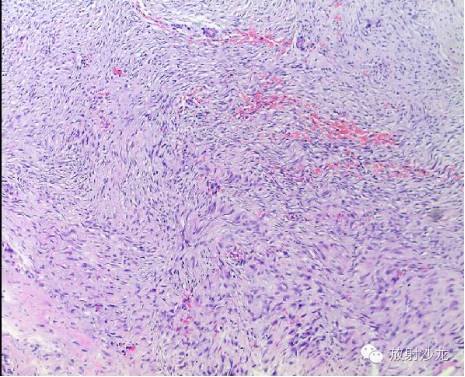

免疫组化结果:EMA(-),Vimentin( ),Ki67( ),CD34(血管 ) ,S100(散在少量 ),SMA(-),Desmin(-).

2. (部分胸骨组织)送检骨、骨髓组织未见著变,周围纤维、横纹肌组织间可见少量瘤组织。

3. (切口皮缘)送检皮肤组织未见著变。